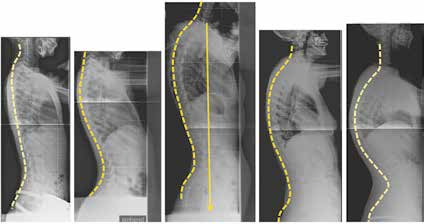

Das dorsale sagittale Wirbelsäulenprofil wird von einer großen Bandbreite an beschwerdefreien Formen geprägt. Ein direkter Zusammenhang zwischen Form und Funktion darf angenommen werden, während die Wahrscheinlichkeit für Beschwerden für den einzelnen Patienten kaum vorhersehbar ist. Werden dagegen Beschwerden diagnostiziert, so kann die Wirbelsäulenstatik in vielen Fällen als gutes Erklärungsmodell herangezogen werden (Abb. 2).

Die erst gegen Ende der Pubertät auftretende Hyperkyphose des Morbus Scheuermann (Abb. 3) entzieht sich durch den Zeitpunkt ihres Auftretens und damit ihrer späten Diagnostik einer effektiven Orthesenbehandlung 10 11 12. Das Potenzial der Orthesenversorgung zur Verhinderung einer Kyphoseprogredienz ist jedoch in Einzelfällen zu nutzen. Besonders Kyphosen im kaudalen Brustwirbelsäulenbereich bieten dabei günstige Hebelverhältnisse.

Die Behandlung von Spondylolyse und Spondylolisthese mittels Orthesen ist aus den Behandlungsempfehlungen weitgehend verschwunden 13 (Abb. 4). Dies ist nur damit erklärbar, dass Orthesen so dargestellt werden, als seien sie zur Ruhigstellung des gesamten Patienten vorgesehen. Das Gegenteil ist jedoch der Fall: Durch eine lokale Stabilisierung und Wirbelsäulenkorrektur wird eine beschwerdearme Aktivierung der Patienten erst wieder möglich.